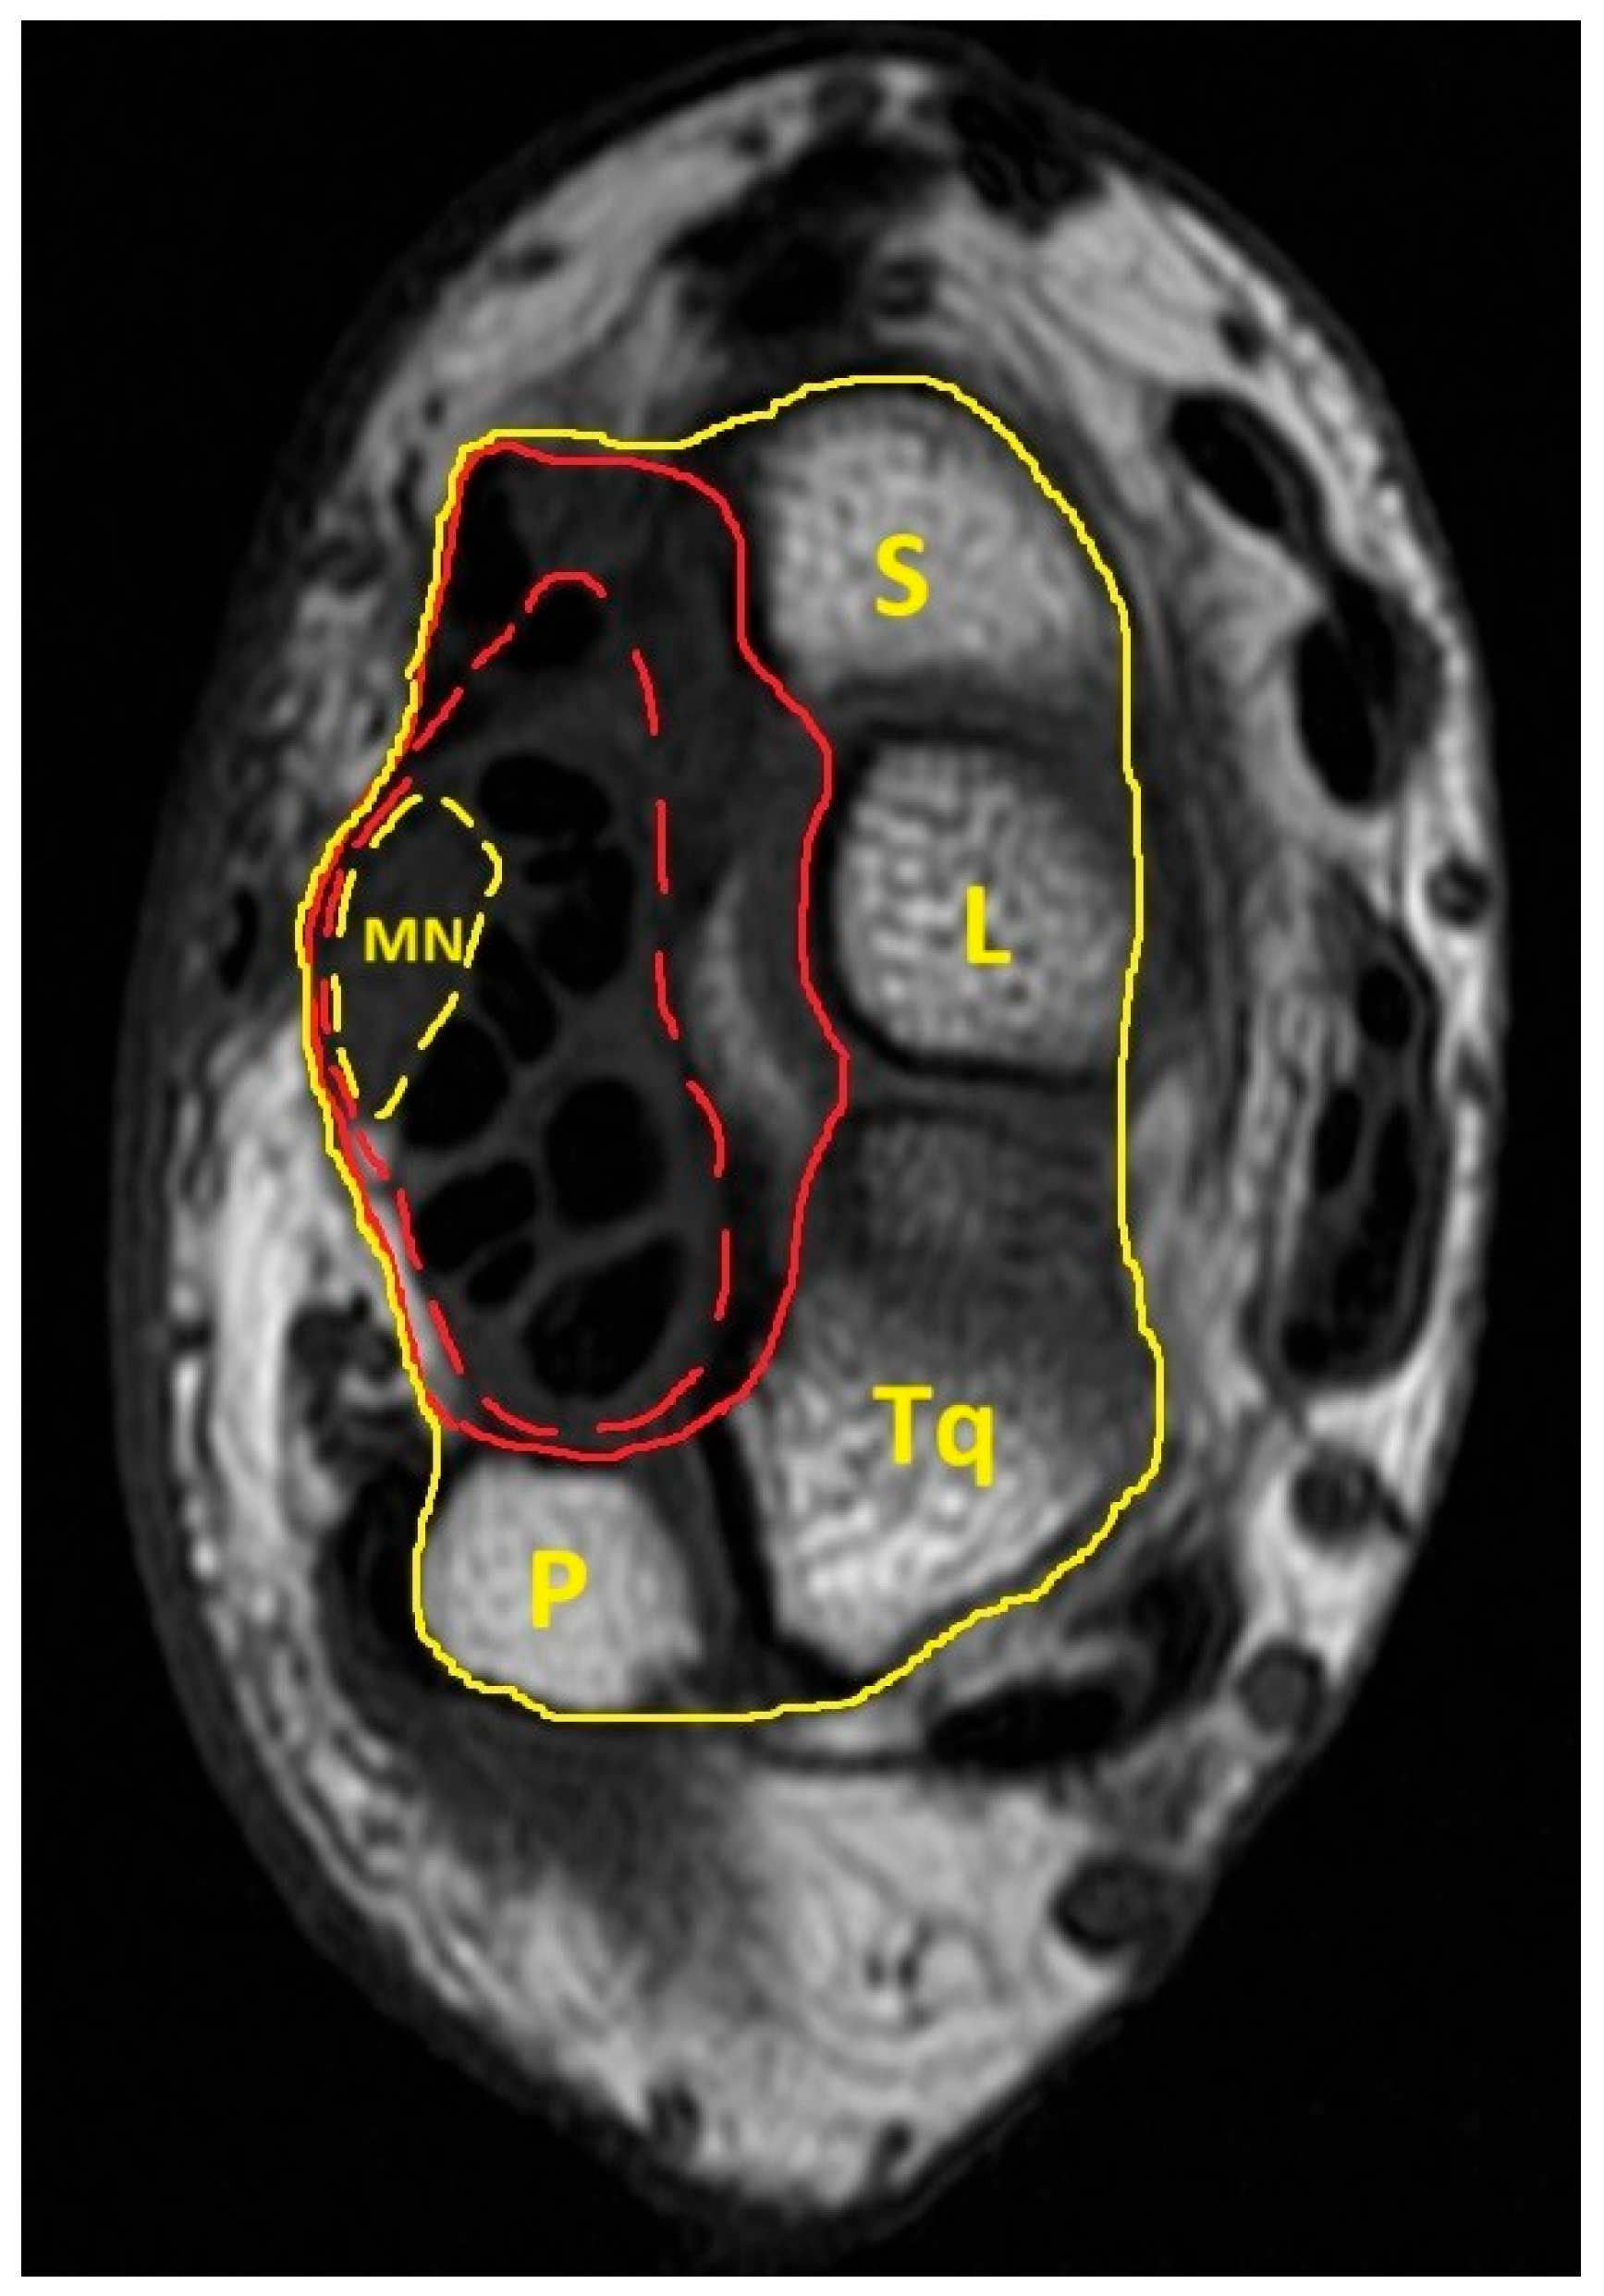

| MN | Median nerve |

| MICB | Most interior carpal boundary |

| ICB | Interior carpal boundary |

| ECB | Exterior carpal boundary |